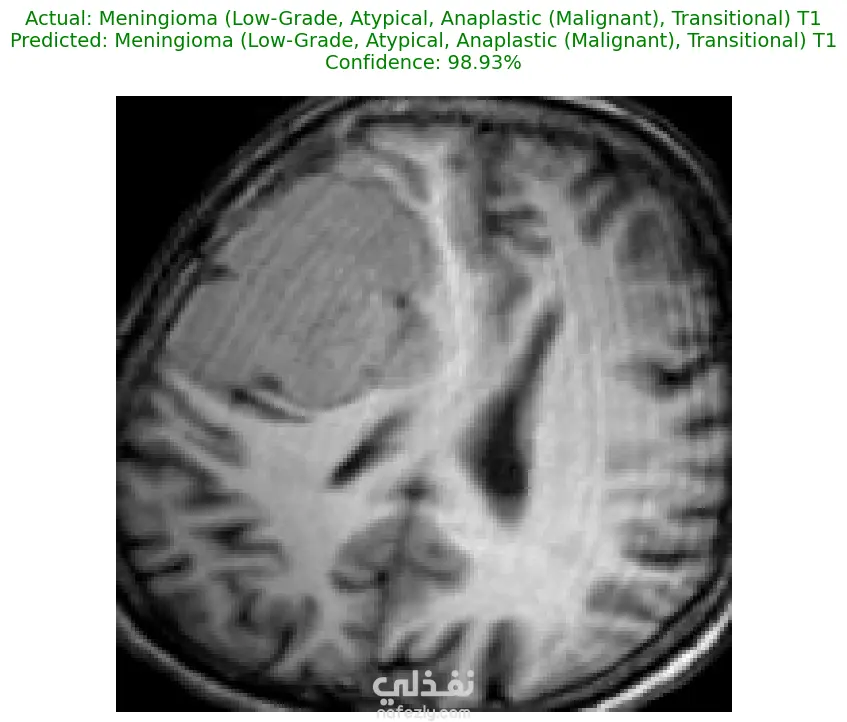

الوصف: قمت بتطوير نموذج تعلم عميق (CNN) قادر على التمييز بين 27 فئة مختلفة من الأورام والحالات الطبيعية بدقة تصل إلى 93%. شمل المشروع مراحل معالجة البيانات الضخمة، تنظيفها وموازنتها، وتصميم معمارية مخصصة لضمان الكفاءة العالية وتقليل استهلاك الذاكرة. المميزات التقنية: دقة استثنائية: حقق النموذج دقة تصل إلى 93% على بيانات التحقق (Validation Accuracy). معالجة البيانات الضخمة: تم العمل على قاعدة بيانات ضخمة، مع تطبيق استراتيجيات موازنة البيانات (Data Balancing) لضمان عدم انحياز الموديل. معمارية مخصصة: تم تصميم شبكة CNN تدعم تقنيات Batch Normalization لتسريع التعلم و Global Average Pooling لتقليل استهلاك الذاكرة وضمان استقرار النموذج. معالجة الصور: استخدام تقنيات OpenCV لقص الصور (Cropping) وإزالة الهوامش غير الضرورية لتركيز الموديل على منطقة الورم فقط. الأدوات والتقنيات المستخدمة: لغة البرمجة: Python. المكتبات الأساسية: TensorFlow / Keras. معالجة الصور: OpenCV & PIL. تحليل النتائج: Scikit-learn (Confusion Matrix & Classification Report). البيئة البرمجية: Google Colab (GPU Acceleration). النتائج المحققة: نموذج قادر على التعرف على أنواع نادرة من الأورام بدقة عالية. تقرير فني يوضح أداء الموديل لكل فئة (Precision & Recall). ملف نموذج جاهز للنشر (Deployment) بصيغة keras الحديثة. يمكنكم الاطلاع على الكود المصدري كاملاً والرسوم البيانية لتقييم أداء النموذج عبر رابط GitHub المرفق، كما يتوفر رابط تحميل النموذج المدرب داخل ملف الشرح.